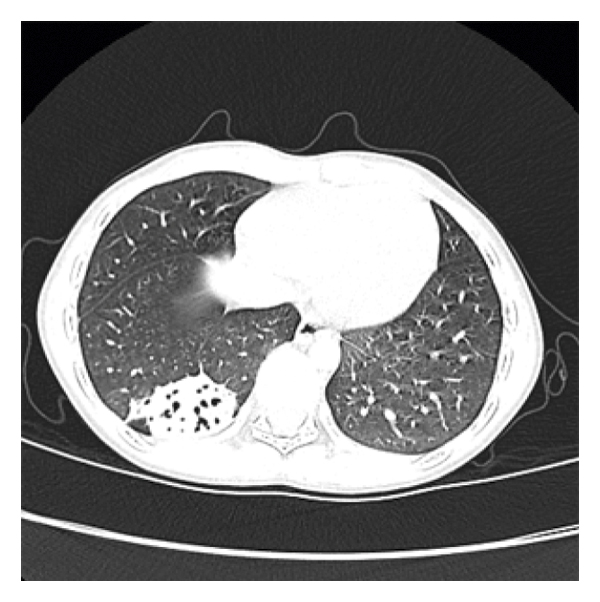

Patients characteristics are listed in Table 1. The five patients comprised four boys and one girl with ages ranging from 15 months to 13 years (mean: 6.7 years). The FB identified included a sunflower seed, teeth, two nut, and a tapioca pearl (see Figure 1). The patients presented with recurrent cough, fever, or wheezing; one patient also experienced hemoptysis. Physical examination found wheezing in two cases, wet rales in one case, and decreased breath sounds in one case. One patient had basic disease, and the others were normal. None had histories of typical aspiration. The FB location was the left lower lobe in two patients, and the right lower lobe in three patients. CT showed inflammation, emphysema, and localized bronchiectasis. Bronchographic examination revealed granulation tissue formation in three patients. Repeated X-ray examination showed that bronchiectasis disappeared after 1 or 6 months. In one case, the patient experienced neither fever nor cough for 3 years after removal of the FB and refused repeat X-ray examination.

In our study, the mean age of patients with bronchiectasis due to FB was higher than that of all patients with FB. In addition, all the patients do not have histories of FB aspiration. The FBs were usually organic. CT revealed that bronchiectasis caused by FB was localized cylindrical bronchiectasis, mainly located in the lower lobes.